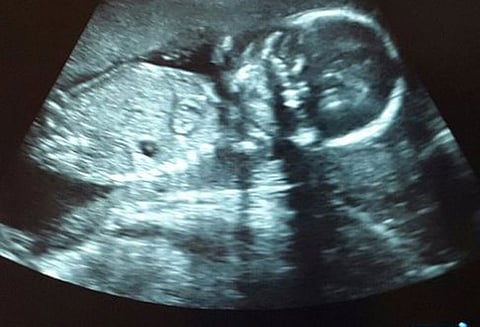

மும்பையை சேர்ந்த 13 வயது சிறுமி அவரது உறவுக்கார வாலிபரால் கற்பழிக்கப்பட்டார். சமீபத்தில் அந்த சிறுமியின் அடிவயிற்று பகுதியில் பயங்கர வலி ஏற்பட்டது. மருத்துவ பரிசோதனையில், அவர் 26 வார கர்ப்பிணியாக இருப்பது வெளிச்சத்துக்கு வந்தது. இந்தியாவை பொறுத்தமட்டில் 20 வாரத்துக்கு மேற்பட்ட கருவை கலைக்க சட்டத்தில் அனுமதி இல்லை.

ஆகையால், சிறுமியின் வயதை காரணம் காட்டி, அவருக்கு கருக்கலைப்பு செய்ய அனுமதி கோரி சிறுமியின் பெற்றோர் தரப்பில் மும்பை ஐகோர்ட்டில் மனு தொடரப்பட்டது. இதனை நேற்று பரிசீலித்த நீதிபதிகள், சிறுமியின் தற்போதைய உடல்நிலையை ஆராய்ந்து அறிக்கை சமர்ப்பிக்குமாறு கே.இ.எம். ஆஸ்பத்திரி டாக்டர்களுக்கு உத்தரவிட்டனர்.